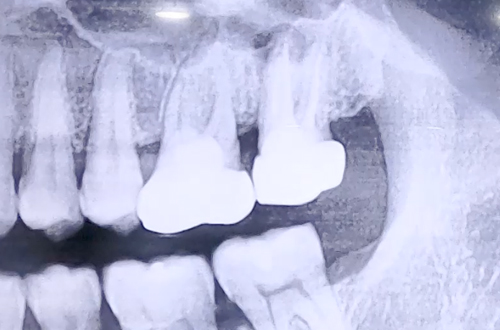

어금니 염증치료 및 발치, 임플란트 사례

더 튼튼하고 효율적인 임플란트 치료를 위해 CT 촬영으로 염증의 위치를 정확하게 파악하는 정밀검사를 더하였고, 염증을 제거해준 뒤 비교적 튼튼히 남아있는 잇몸뼈 쪽으로 식립 후 뼈이식으로 단단히 해 드렸습니다.

꼼꼼한 검진의 중요성을 일깨울 수 있었던 케이스로, 최종 보철까지 마무리되면 다시 진료일지로 찾아뵙겠습니다. ^^